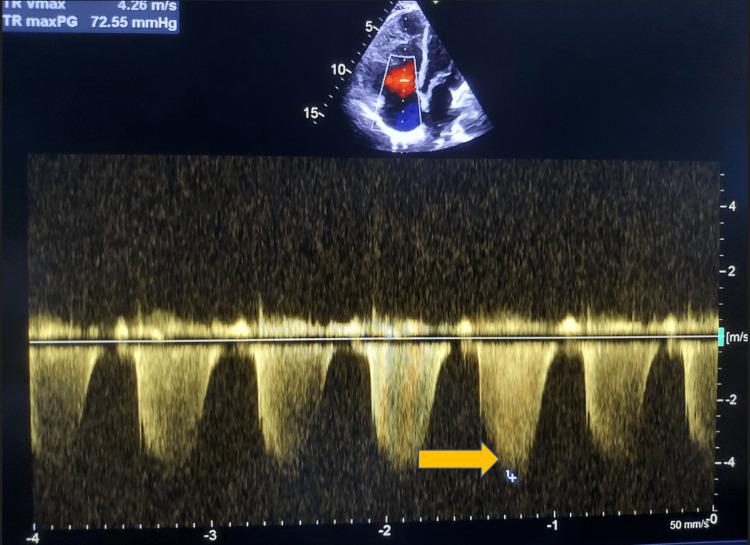

Pulmonary arterial hypertension (PAH) is an uncommon manifestation of systemic lupus erythematosus (SLE), affecting about 0.5% to 23.3% of the population worldwide. The causes of PAH associated with SLE are multifactorial. While it is generally associated with a full-blown picture of SLE, it may rarely be the presenting manifestation of the disease. We describe the case of a middle-aged woman who presented with features of severe PAH due to SLE. She was treated with vasodilators and immunosuppression (steroids and mycophenolate mofetil), with a partial response to treatment at six months follow-up.

肺动脉高压(PAH)是系统性红斑狼疮(SLE)的一种罕见表现,在全球约0.5%至23.3%的人群中出现。与SLE相关的PAH病因是多因素的。虽然它通常与典型的SLE症状相关,但也可能极少作为该疾病的首发表现。我们描述了一名中年女性的病例,她因SLE出现了严重PAH的症状。她接受了血管扩张剂和免疫抑制治疗(类固醇和霉酚酸酯),在六个月的随访中治疗有部分反应。